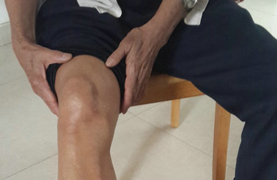

【易发部位】脚拇指关节、拇趾跖关节、跗跖关节、踝关节、手指关节,掌指关节、腕关节、肘关节、膝关节、耳廓。

【典型症状】膝肿痛、关节痛、关节肿胀、尿酸高、发热、厌食、鹤膝风。